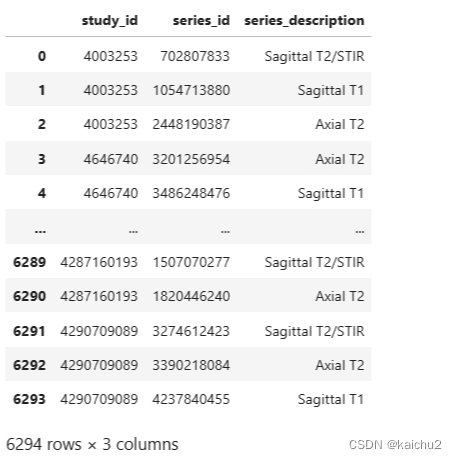

2.2、train/test_series_descriptions说明

这个文件是关于训练数据的描述:主要有

['study_id', 'series_id', 'series_description']

在RSNA比赛中,‘study_id’, ‘series_id’, 'series_description’分别表示:

- ‘study_id’: 研究ID,用于唯一标识一个医学影像研究项目。

- ‘series_id’: 系列ID,用于唯一标识一个医学影像研究中的特定序列或扫描类型。

- ‘series_description’: 系列描述,描述了该系列的具体信息,例如扫描技术、扫描范围等。

使用study_id和series_id作为唯一标识符来检索特定的医学影像图片,因为图片就是根据study_id/series_id层级存放的,而series_description表示study_id/series_id组合下图片的分类标签。

通过对series_description列去重主要有下面三个类别:

这三个术语是MRI扫描中的一些序列类型。

Axial T2: 轴向T2加权成像是一种MRI扫描序列,它对组织的T2弛豫时间敏感。这种序列可以提供高对比度的图像,特别是对于水分含量较高的组织,如脑脊液、肌肉和肿瘤。

Sagittal T1: 矢状T1加权成像也是一种MRI扫描序列,它对组织的T1弛豫时间敏感。这种序列可以提供高对比度的图像,特别是对于脂肪和钙化等物质。

Sagittal T2/STIR: 矢状T2/短TI反转恢复(STIR)成像是一种MRI扫描序列,它结合了T2加权成像和STIR技术。STIR技术可以抑制脂肪信号,从而提供更清晰的图像。这种序列常用于检测炎症、水肿和肿瘤等病变。